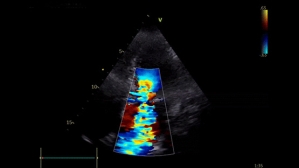

Ce patient de 86 ans est hospitalisé pour des lésions dermatologiques aspécifiques. Il présente plusieurs facteurs de risque cardiovasculaire : un tabagisme ancien, un diabète de type 2, de l’hypertension, une dyslipidémie et un surpoids. Il est également atteint d’une surdité non appareillée et d’une maladie aortique.